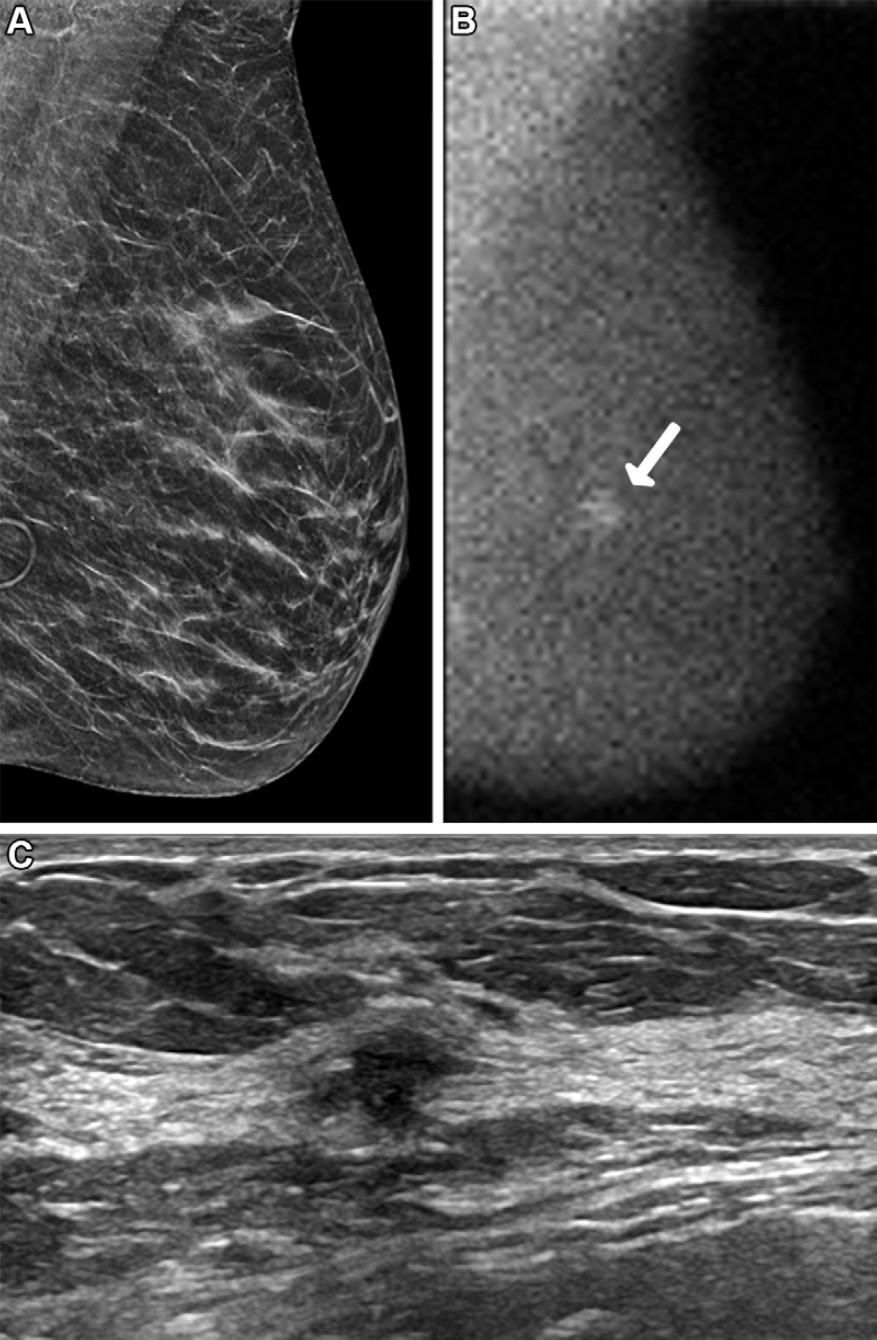

Two radiologists interpreted the standard-dose and simulated half-dose exams using the postprocessing algorithm in either a "default mode" (the software reduced noise in the image using a mathematically calculated factor) or a "preferred filtered" mode (the software segmented the breast tissue on the image, measured the counts per pixel, and adjusted the algorithm setting based on count density).

The researchers found that the simulated half-dose images weren't conspicuous enough for the radiologist readers: The readers rated the simulated half-dose images as poorer in 92 of 100 interpretations, equivalent in six, and better in two, compared with the standard-dose images. However, the half-dose images processed with the algorithm were better visualized.